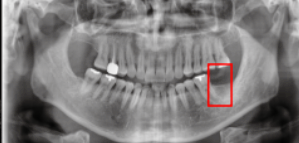

Before (전)

내원하신 분은 이미 치아를 발치까지 되어있는 상태였습니다. 치아 발치 후 상당 기간을 방치했기 때문에, 뼈이식을 진행해야 하지 않을까 걱정을 하시며 방문하셨는데요.

X-RAY 촬영 결과, 다행히 임플란트 식립을 하기에 잇몸뼈의 상태가 양호하다고 판단되었고, 주변 치아의 방해가 없는 것이 확인되었습니다.

따라서 임플란트를 진행하기로 결정하였습니다.